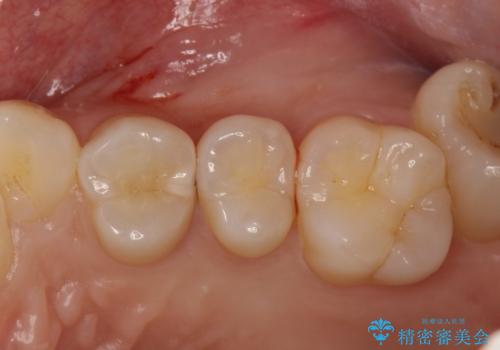

気づかないうちに大きな虫歯が 神経を保存し、セラミックで修復